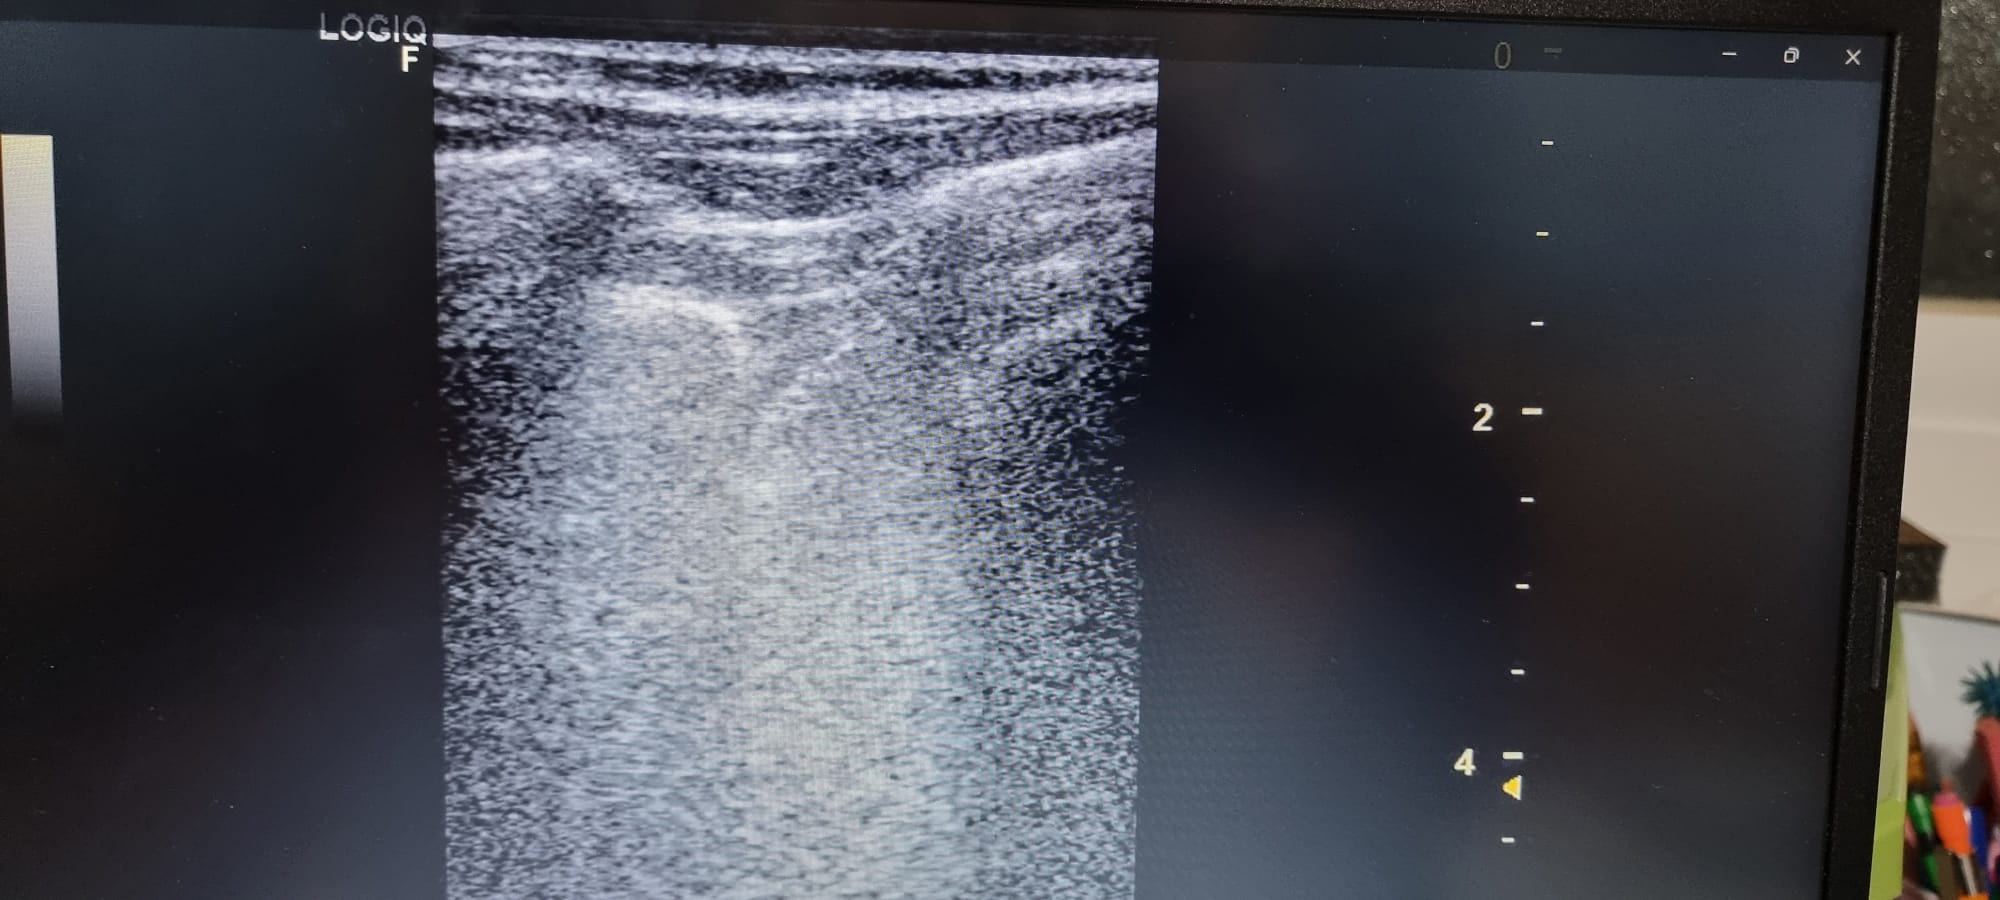

Se observa en base pulmonar izquierda defecto pleural triangullar (comparado con el contralateral).

La ecografía clínica pulmonar, nos aporta gran información que complementa la hipotesis dx, en este caso no acertada porque pensabamos mas en un TEP ya que nunca habiamos visto un derrame pleural en ecografía. Este era mínimo y no detectable con Rx Tx, con los conocimientos de la normalidad pudimos ver que había una imagen patologica comparando con el contralateral.